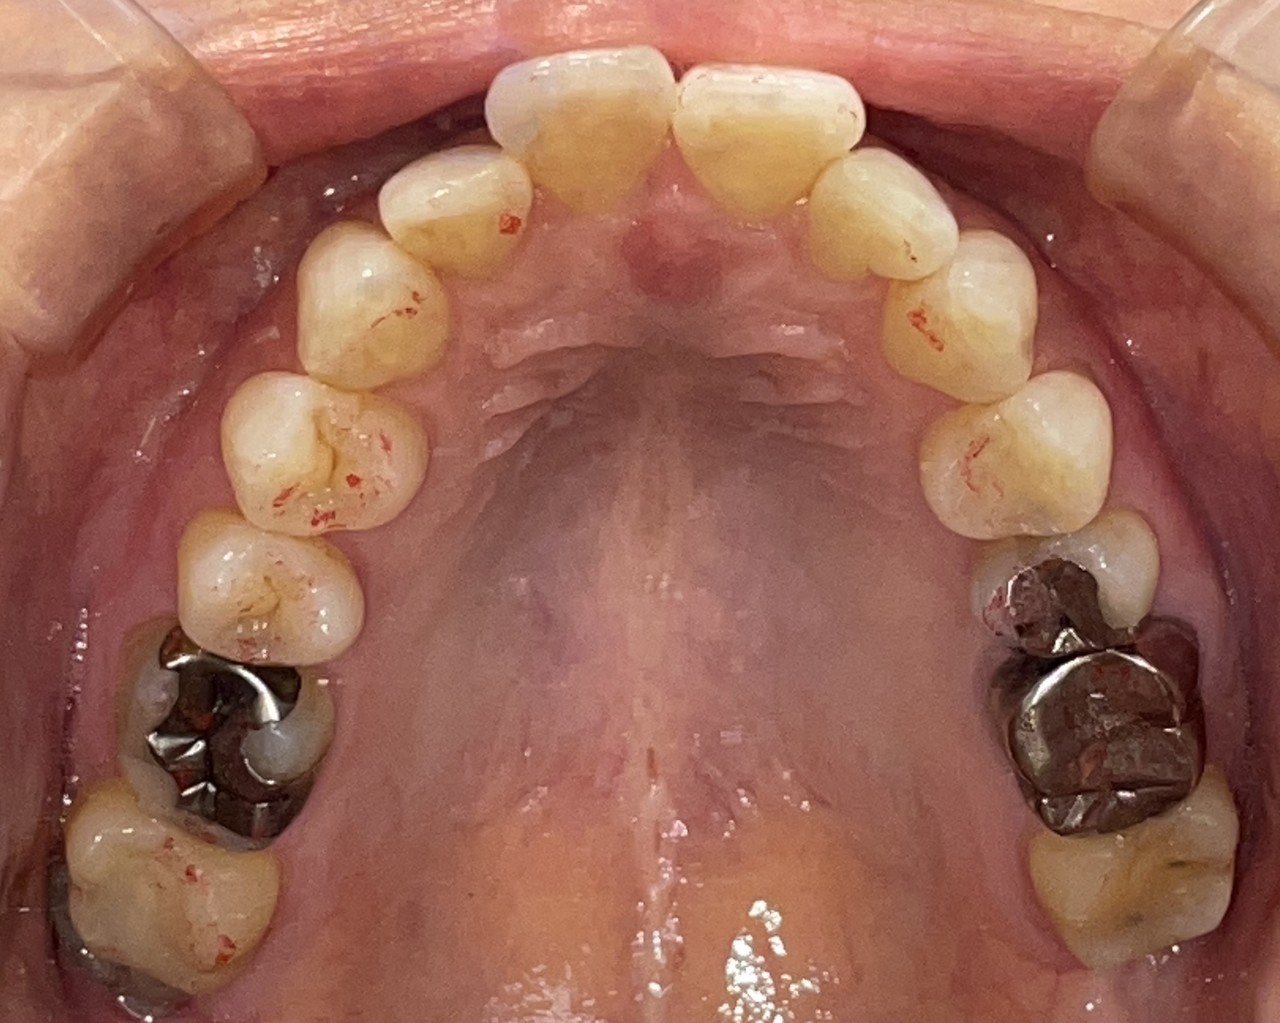

Before

After

矯正の種類 / invisalign GO

年齢・性別 / 50代女性

主訴  /  上下顎前歯の叢生

治療期間 / 7ヶ月

費用 / 簡易検査 5,000円(税別) 精密検査 30,000円(税別)

両顎マウスピース 450,000円(税別) 両顎リテイナー料 40,000円(税別)

※マウスピース交換時別途調節料5,000円(税別)

副作用 / 口内炎・歯の移動に伴う痛み・知覚過敏 ※数日で収まる場合が多いです

リスク / 後戻り防止の為、夜のみマウスピースで保定を指示